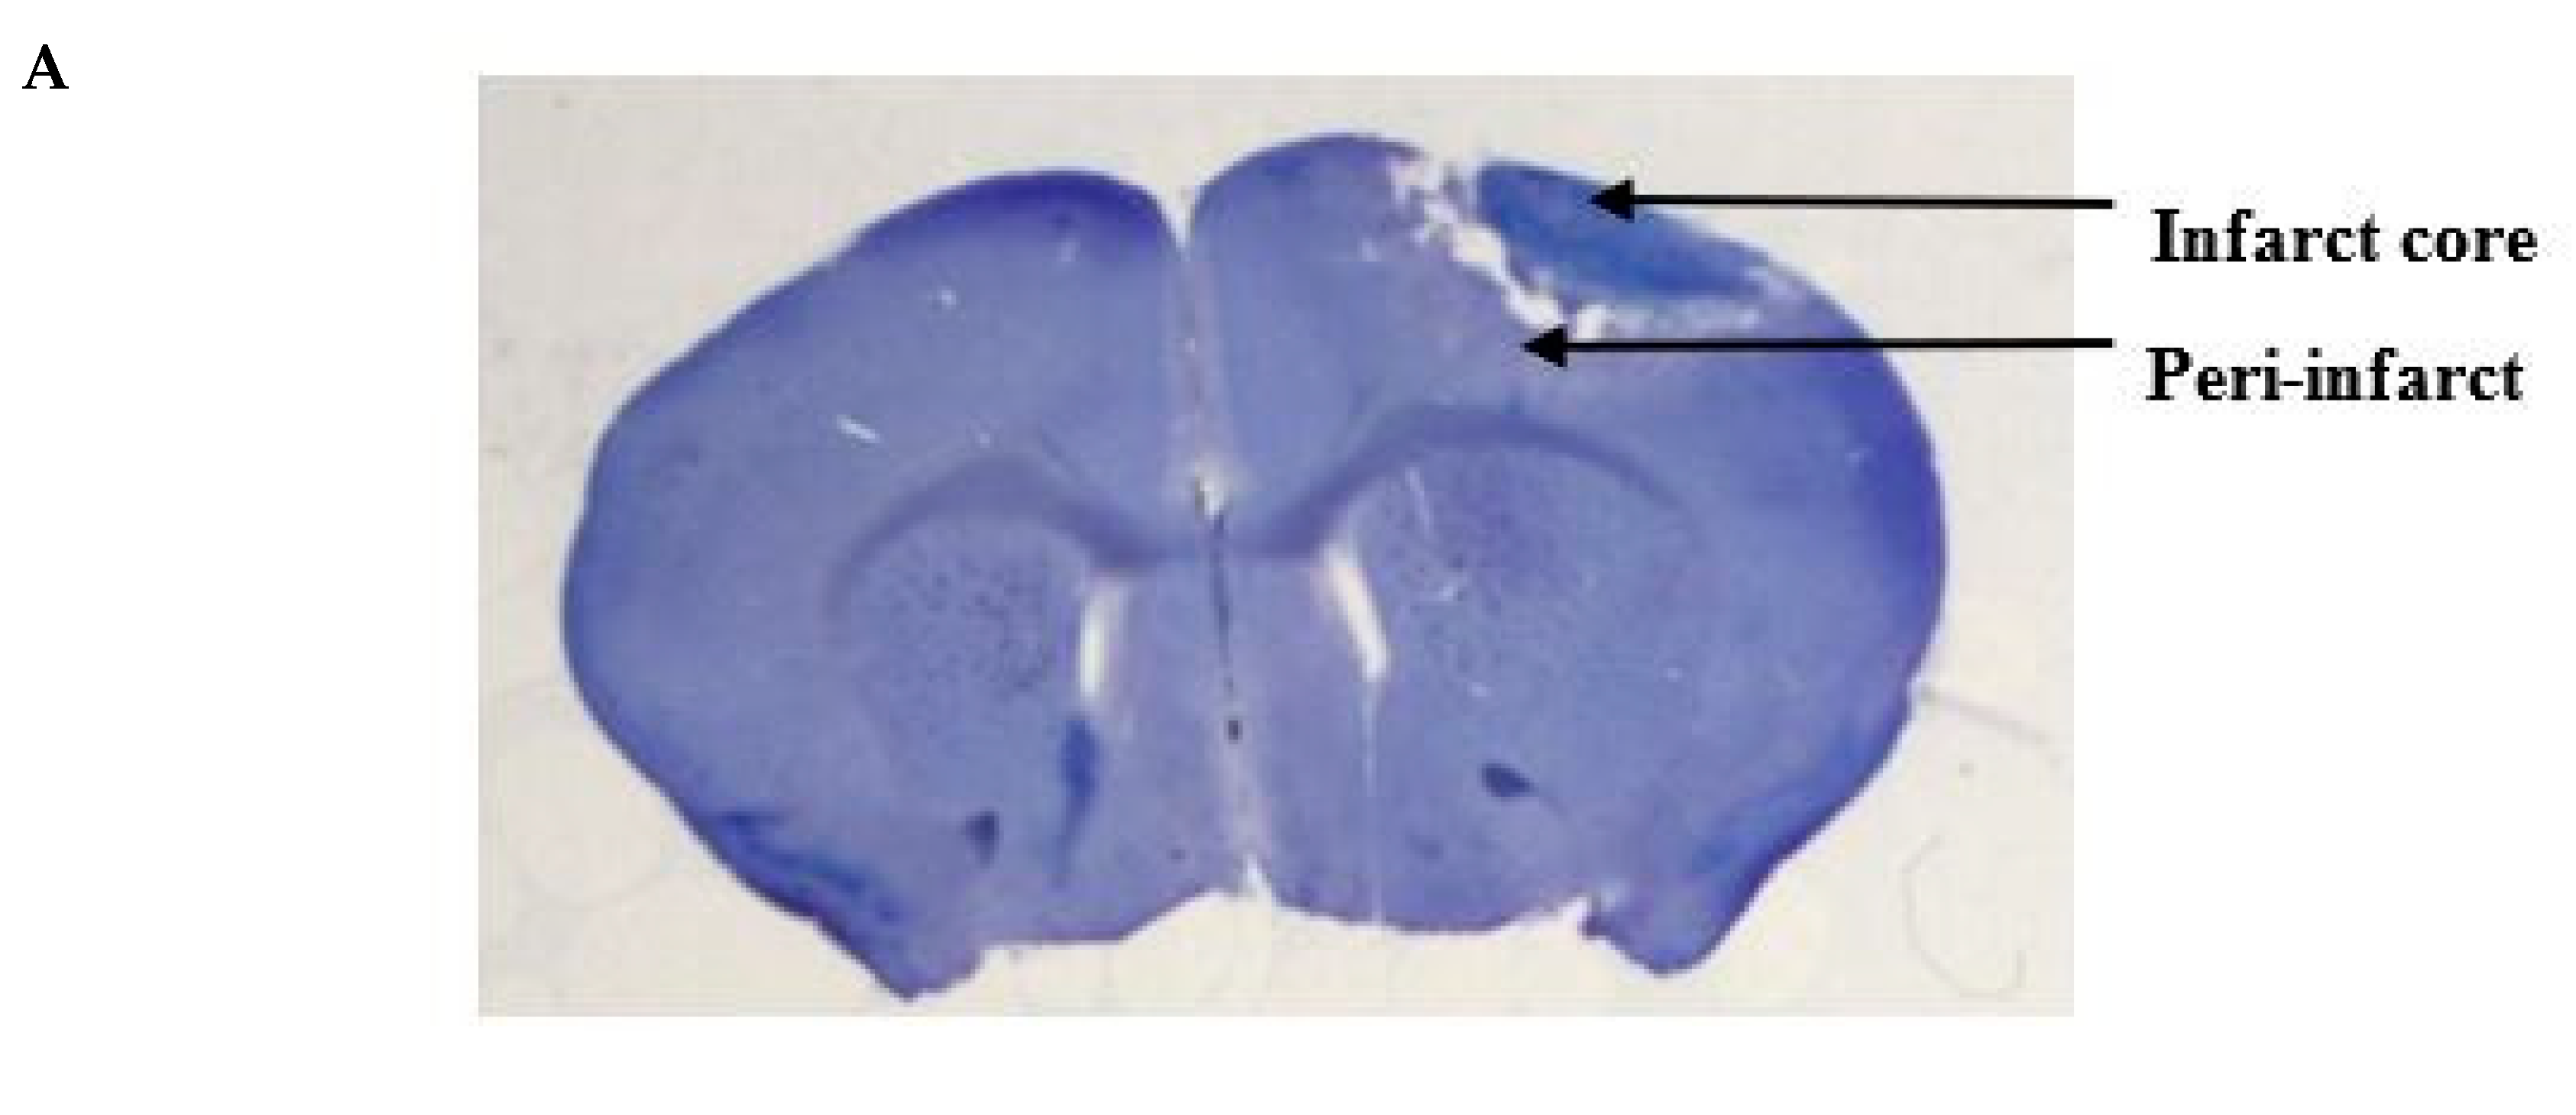

We performed cresyl violet staining to evaluate the extent of the photothrombotic stroke volume and the effect of epicortical application of PbTx-2 on the same (Figure 2A). Coronal sections of 100 μm were collected using a vibratome (Leica VT 1200S). For the infarct volume measurement, brain sections were stained with 0.5% cresyl violet and images were then acquired using a bright-field microscope. The areas of infarct were delineated and quantified using the Image J software (NIH) and infarct volume was calculated by summation of the lesion areas of all sections and integrated by the thickness of the section (Figure 2B). Infarct volumes did not vary significantly between vehicle- and PbTx-2-treated mice (Figure 2C). These results indicate that the timing of PbTx-2 treatment utilized was appropriate for the assessment of promoting functional recovery inasmuch as these treatments did not affect stroke volume.

Histologic assessments after stroke. (A) Representative cresyl violet image showing the infarct and the peri-infarct region. (B) Representative cresyl violet stained-sections of vehicle, 3, 10, 100, 1000 and 3000 pmol PbTx-2, respectively. (C) Quantification of infarct volume. No significant differences in infarct size were detected (one-way ANOVA followed by Dunnett’s post hoc test, 3 pmol PbTx-2 effect, p = 0.993; 10 pmol PbTx-2 effect, p = 0.907; 100 pmol PbTx-2 effect, p > 0.999; 1000 pmol PbTx-2 effect, p = 0.873; 3000 pmol PbTx-2 effect, p = 0.975). Data shown are mean ± SEM of 2 to 7 brains.